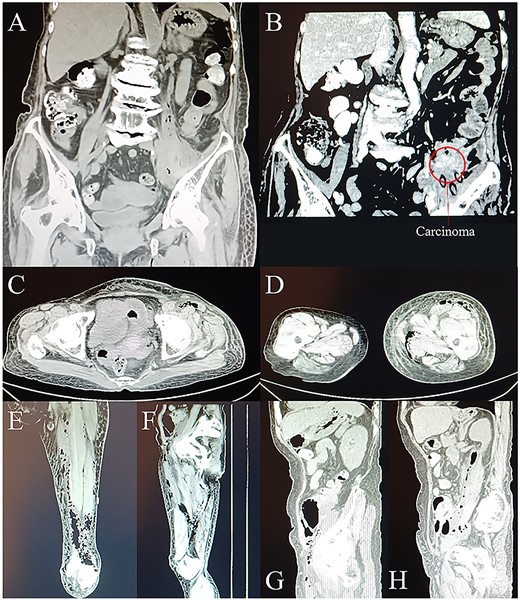

Laboratory examination demonstrated a white blood cell (WBC) count of 32.42*109/L (3.50–9.50*109/L), a procalcitonin (PCT) level of 4.23 ng/ml (<0.05 ng/ml), a hypersensitive C-reactive protein level of >160 mg/L (0.0–5.0 mg/L), and a carcinoembryonic antigen (CEA) level of 136.38 ng/ml (0.0–5.0 ng/ml). A computer tomography (CT) scan revealed swollen, blurred soft tissue with pneumatosis in left psoas major, left lower back, left pelvic cavity, left pelvic wall, left groin region, left thigh—upper left calf, and bowel (probably descending colon) wall thickening and calcification in left lower abdomen accompanied with slightly narrowed intestinal lumen in the same segment (Fig. 1). According to the clinical features, principal diagnosis were gas gangrene in the left groin and left thigh and descending colonic cancer perforation with left lower abdominal abscess.

CT scans on day 1. (A) and (B) Coronal planes from CT display abdominal gas formation, abscess and tumor around descending colon. Tumor locates in the left lower abdomen. (C) Transverse, (E) coronal, and (G) sagittal planes from CT display gas extending to and going through the groin area. (D) Transverse and (F) coronal planes from CT display the downward route of gas formation. (H) Sagittal plane from CT displays the involvement of iliopsoas muscle.